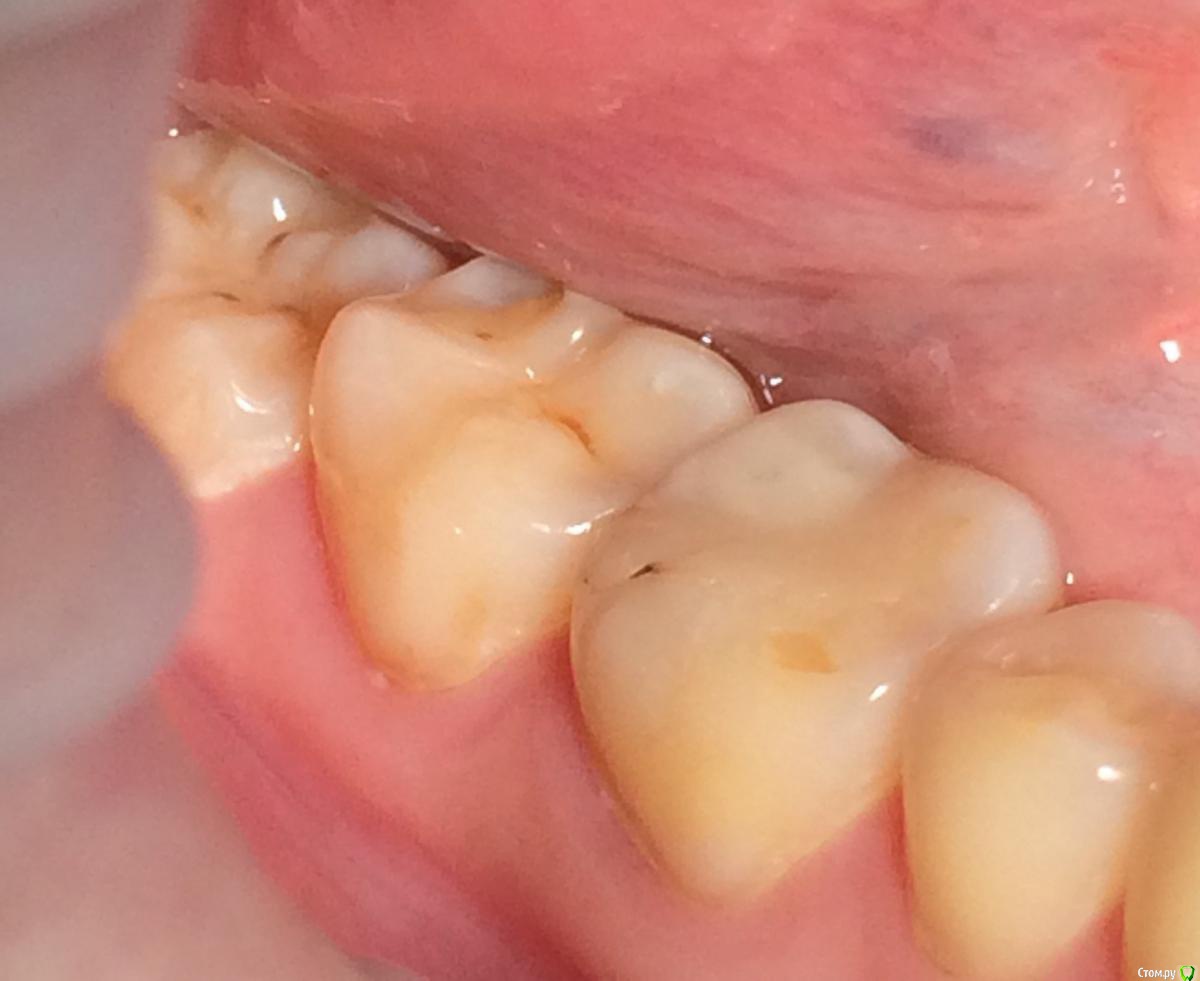

Larnary Опубликовано 28 июля, 2015 Поделиться Опубликовано 28 июля, 2015 (изменено) Добрый день!Ко мне обратилась пациент 1988 гр с жалобой на стираемость зубов и постоянные сколы пломб.Объективно небная поверхность верхних резцов стерта до дентина. Окклюзионная стираемость жевательной группы зубов.Прошу помочь с выявлением причины такой стираемости зубов и оптимальноно метода лечения Изменено 28 июля, 2015 пользователем Larnary Ссылка на комментарий

Larnary Опубликовано 28 июля, 2015 Автор Поделиться Опубликовано 28 июля, 2015 (изменено) Видно окклюзионнык интерференции в области 37 и 47.На днях удален 38 и дальше будут удалены остальные восьмерки. На ТРГ мне видится небольшая ретрузия верхних резцов,дистальный прикус. Так же левпя окклюзионная кривая более выраженная,чем правая Изменено 28 июля, 2015 пользователем Larnary 1 Ссылка на комментарий

Bobby Опубликовано 29 июля, 2015 Поделиться Опубликовано 29 июля, 2015 Фасетки стираемости на нёбных поверхностях верхних резцов и вестибулярных поверхностях нижних резцов обусловлены малым оверджетом - недостаточная щель по саггитали, поэтому и будут колоться реставрации, а ткани зубов истираться. Фрадеани про это на своём курсе рассказывал и показывал видео как это диагносцировать и что с этим делать. Что вообще хочет пациентка и на что готова? Эти вопросы лучше сразу решать на первичной консультации, а то делаете диагностики, всё рассчитываете, распинаетесь, а они потом: "ой, я пока не готов/а к такому плану лечения" и всё заканчивается композитной мазнёй в другой клинике. 5 Ссылка на комментарий